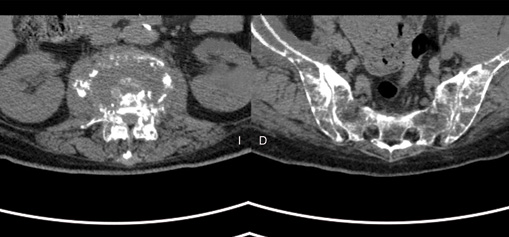

Paciente de sexo femenino de 62 años de edad, mexicana, que se presenta al servicio de urgencias por alteración del estado de alerta, desorientación, somnolencia, a su ingreso con fiebre de hasta 40 °C, TA 90/mm/Hg, FC 120x’, FR 20x’, alucinaciones visuales y lenguaje incoherente, rigidez de nuca y signos de Brudzinski y Kernig positivos, con disminución simétrica de la fuerza en las cuatro extremidades 3/5, sin focalización, al examen de fondo de ojo no se identificó papiledema. Su historia médica previa incluye historia de histerectomía por miomatosis uterina de grandes elementos, refirió lumbalgia desde 2 semanas previas, sin limitación funcional y sin haber recibido tratamiento, no ingesta de medicamentos, drogas o herbolaria y sin otros patológicos relevantes. Se identificó leucocitosis por neutrofilia, se obtiene líquido cefalorraquídeo (LCR) y se identifica turbio, con hipoglucorraquia de 13 mg/dl (rango 40-70), hiperproteinorraquia de 3200 mg/dl (rango 20-45), pleocitosis de predominio polimorfonuclear 85 % y presencia de cocos Gram positivos. Se hace el diagnóstico de meningitis bacteriana y se inicia tratamiento con ceftriaxona, vancomicina y ampicilina, no desarrolló crecimiento bacteriano en cultivo. La paciente presentó resolución de los signos meníngeos, sin embargo, al volver a estado consciente aqueja de lumbalgia intensa, dolor en miembros pélvicos y paraplejía. Se identifica en radiografía simple y tomografía la presencia de fractura por compresión a nivel de T12 y L3 y lesiones líticas en cuerpos vertebrales dorsales y lumbares, cráneo, húmeros, sacro y pelvis (figuras 1 a 3) fue valorada por neurocirugía considerándose no candidata a descompresión quirúrgica.